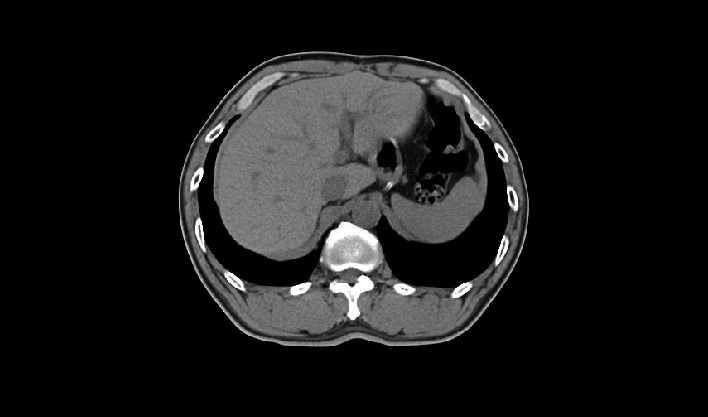

快速扫描,精准“冻结”器官运动瞬间,高清呈现亚毫米结构,为心血管等系统疾病早期诊断和治疗提供黄金窗。

一次屏气快速扫描

精准“冻结”运动瞬间

避免呼吸伪影

百万像素成像

1024x1024重建矩阵结合薄层成像,快速锁定微小病灶(如早期肿瘤、卒中病灶),助力急诊创伤、肿瘤筛查、卒中救治的“分秒必争"。